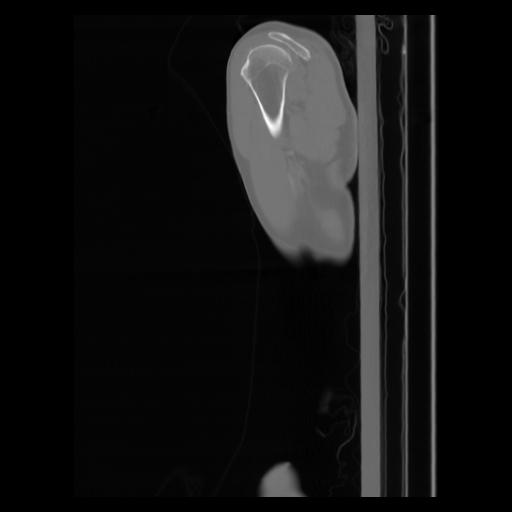

30 CUERPO,CE,Sagittal,3.000,CUERPO,Sagittal,